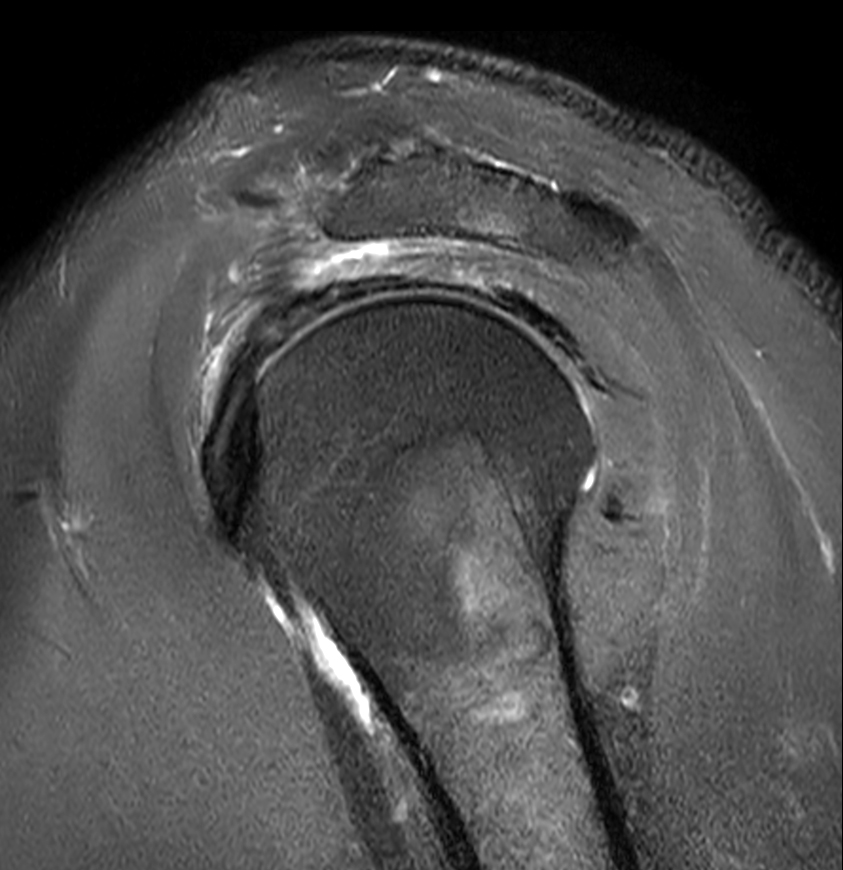

High resolution imaging with the dS 16ch Shoulder coil and Compressed SENSE